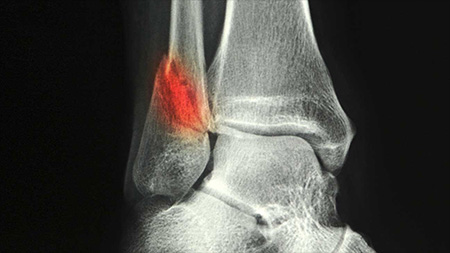

Basically, instead of breakage on two bones - 5th metatarsal and bottom of the fibula, I've actually managed to break five bones. I've also broken a bone in my third metatarsal and have two breaks through my interior ankle. I'm under strict orders to have NO weight bearing on my injured leg for at least six weeks and he actually offered me the option of getting a plaster or fiberglass hard cast if I felt it would be a better alternate for me. But since I'm doing better with the walking cast with my orthotic inserted, I'm going to try and stick with the removable cast.

The thing that frightened me was his talk of possible shifting of one of the breaks in the ankle, which would require surgery and pins to stabilize if it happened. That crushed my normal optimism into the depths of black despair for a while. He also mentioned that a knee walker scooter might be helpful but that they were expensive and I probably should also check secondary sellers (I actually ended up ordering a new one from Target for slightly over $100, so not bad). He said I may need to use it for up to eight weeks.